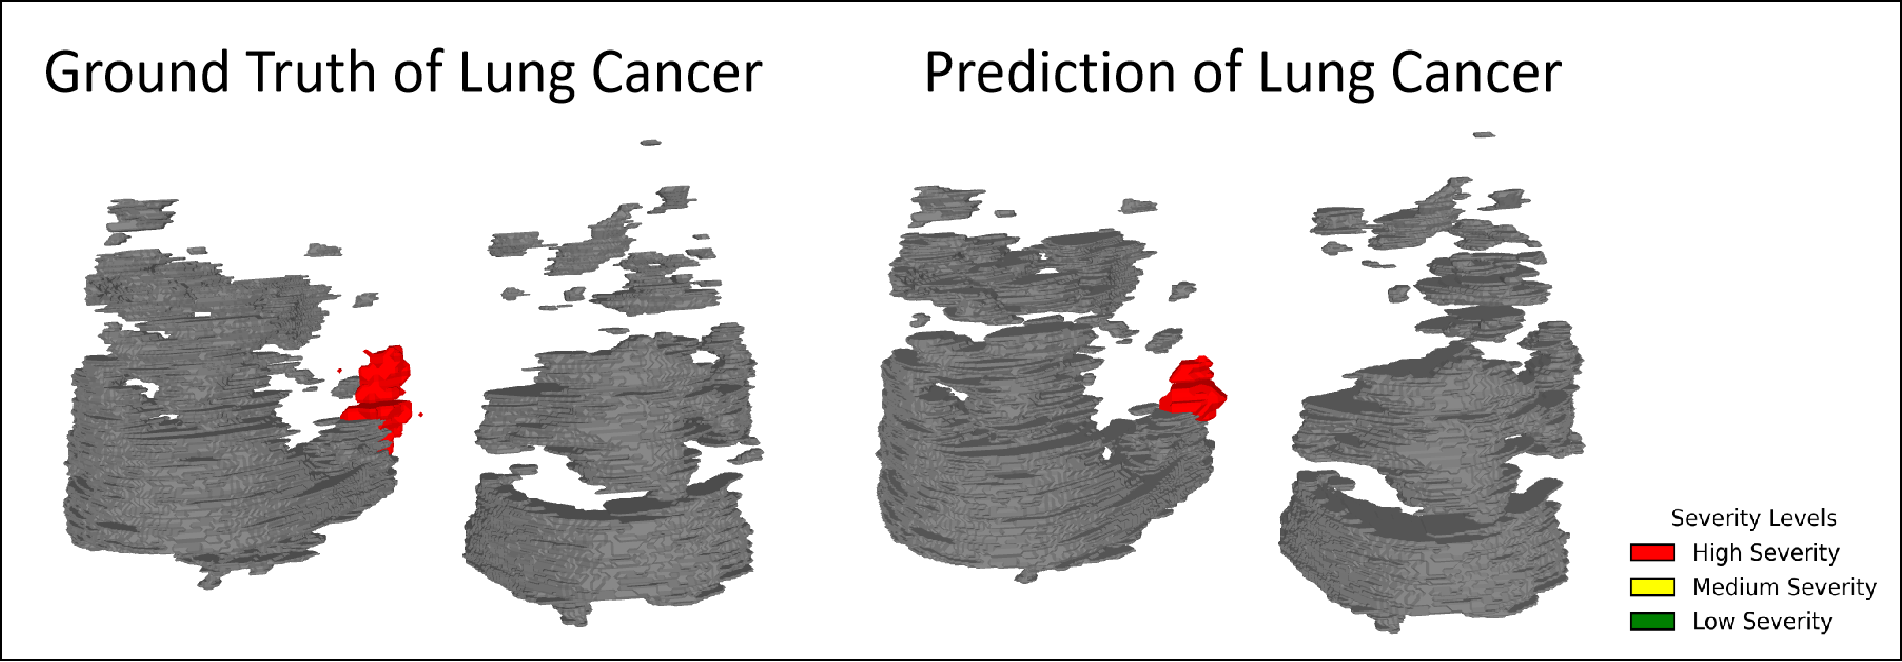

TARU-Net achieves strong performance across both lung cancer and COVID-19 pneumonia datasets:

TARU-Net achieves strong performance across both lung cancer and COVID-19 pneumonia datasets:

Color-coded severity: Red (severe), Yellow (moderate), Green (healthy tissue).

3D reconstructed predictions from TARU-Net for lung cancer cases.